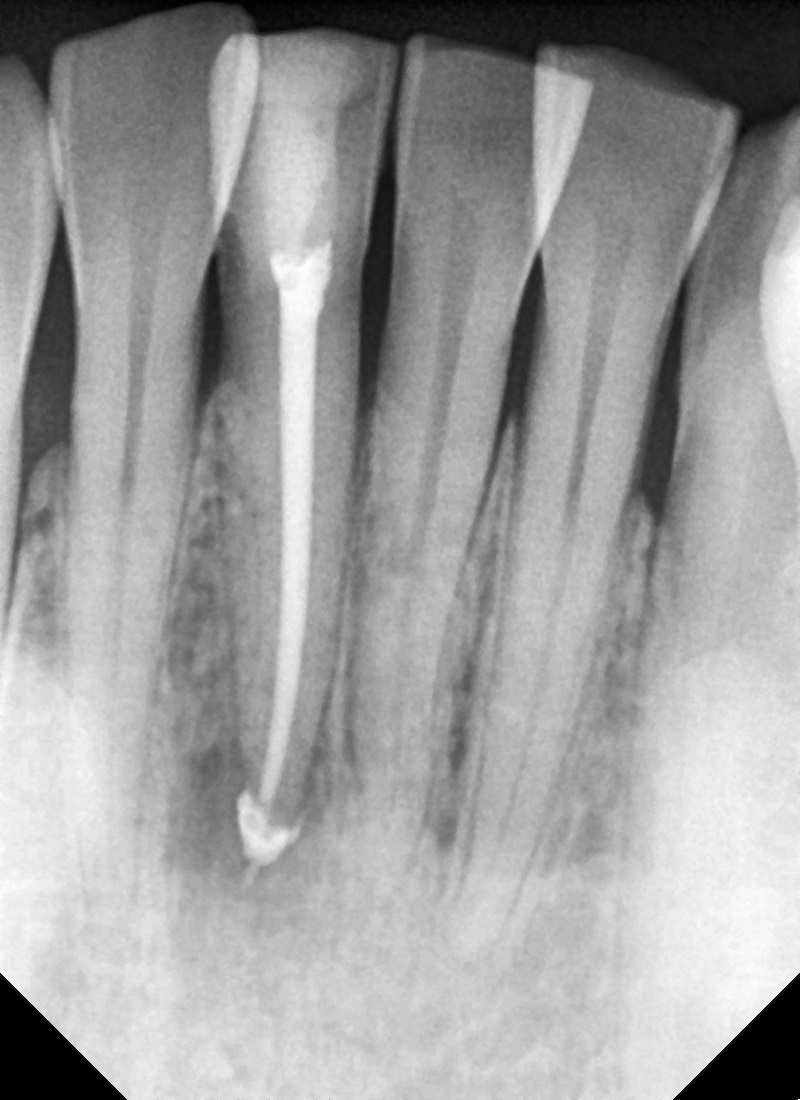

다행히 첫날부터 신경관을 확보할 수 있었고

다음날부터 통증은 완화되었습니다.

증상 체크를 하며 내원 4회차 만에 신경치료를 완료할 수 있었습니다.

뿌리 쪽 염증으로 인해 주변 골이 녹아있는 상태에서 뿌리 외부와 내부를

차단하기 위해 뿌리 주변을 약재가 막게끔 충분히 밀봉을 했습니다.